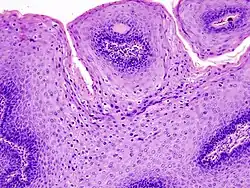

The diagnosis of genital warts is most often made visually, but may require confirmation by biopsy in some cases.[21] Smaller warts may occasionally be confused with molluscum contagiosum.[20] Genital warts, histopathologically, characteristically rise above the skin surface due to enlargement of the dermal papillae, have parakeratosis and the characteristic nuclear changes typical of HPV infections (nuclear enlargement with perinuclear clearing). DNA tests are available for diagnosis of high-risk HPV infections. Because genital warts are caused by low-risk HPV types, DNA tests cannot be used for diagnosis of genital warts or other low-risk HPV infections.[4]